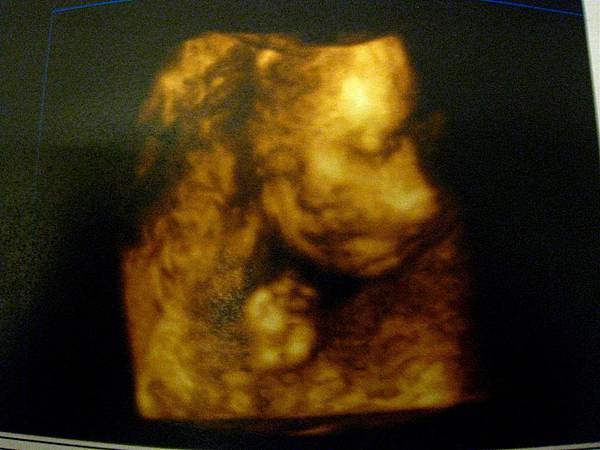

28週拍攝四D的糖果妹妹:

閉著眼睛,文文靜靜的模樣。